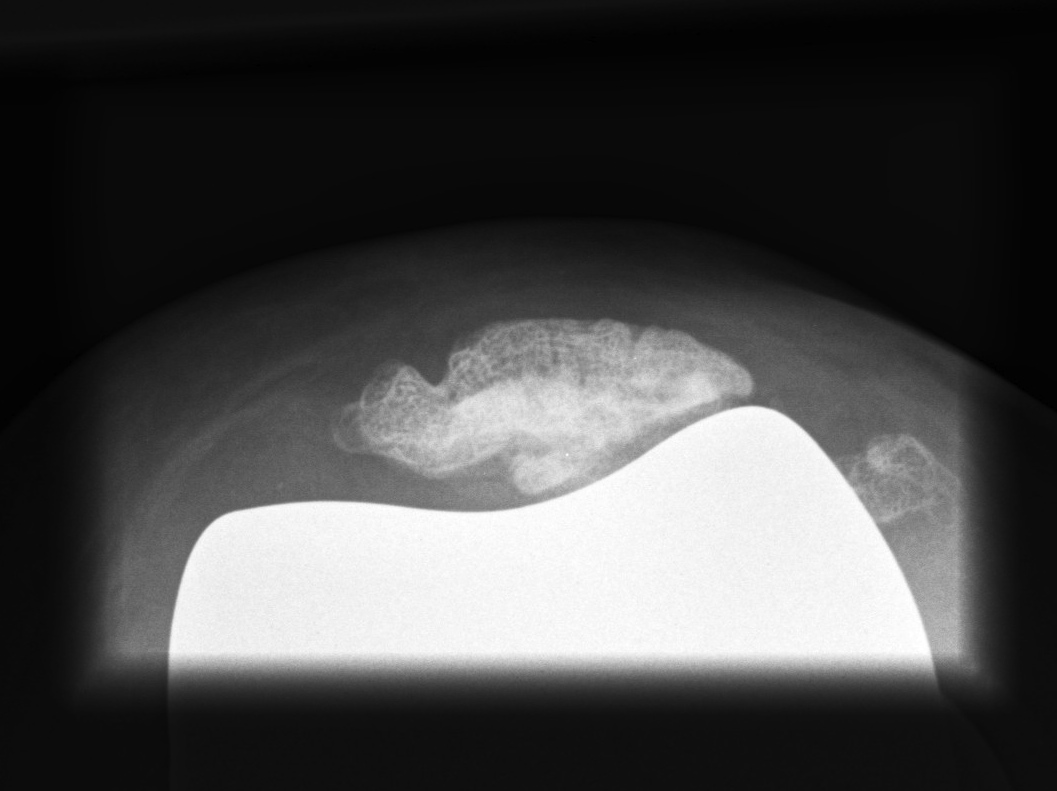

Patella

Options

1. > 10 mm bone remaining

- can resurface

2. Ignore